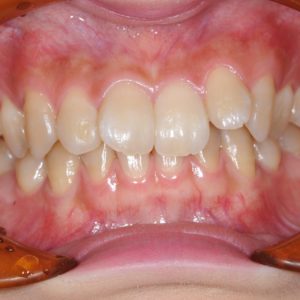

虫歯の治療、矯正の相談をご希望され来院されました。お口の中を診査(レントゲン写真、口腔内写真、視診)させていただいたところ、虫歯については問題なくきれいに歯磨きされているようでした。 正面から見るとジグザグしており、お口 […]

全体的な歯並びの矯正治療を行いました。治療期間は3年間。

ジグザグの歯並びを気にされてご来院されました。. 見た目の問題も大切ですが、それ以上に清掃がしにくいために虫歯・歯周病に非常になりやすく、不正咬合(良くないかみ合わせ)は顎の関節に負担をかけてしまい顎関節症を引き起こす可 […]

歯の大きさに対する顎の大きさのスペース不足により歯が並びきらず、ジグザグの歯並びおよび上の前歯が出っ歯になっていました。 左右4番の歯を抜歯することにより歯を並べるスペースを確保し、歯並びを揃えました。 全体の歯並びが綺 […]